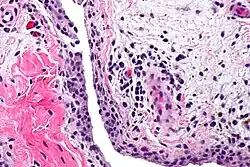

Синови́т, лат. synovitis (от лат. (membrana) synovialis — синовиальная оболочка и суффикса -itis, обозначающего воспалительный процесс) — воспаление синовиальной оболочки, ограниченное её пределами и характеризующееся скоплением выпота в выстилаемой ею полости (в синовиальной сумке, влагалище сухожилий, суставной полости)[1][2].